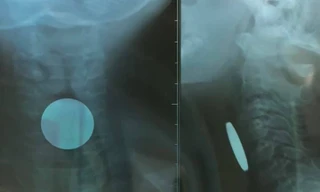

TPO - Bệnh nhi được đưa đến bệnh viện trong tình trạng khó thở. Kết quả chụp X-Quang cho thấy có một dị vật mắc trong cổ bé rất to, chiếm hết lòng đầu trên thực quản, gần ngay ngã 3 thông với đường thở.

TPO - Cháu P. liên tục đau ở vùng cổ và có những dấu hiệu bất thường. Gia đình sau đó đã đưa đi khám và bất ngờ phát hiện một đồng xu nằm trong thực quản.

TPO - Bằng những thao tác chuyên nghiệp, nữ bác sĩ đã khéo léo kéo bật đồng xu mắc trong miệng em bé. Theo dõi những thao tác này mọi người khổng khỏi hồi hộp và thót tim.